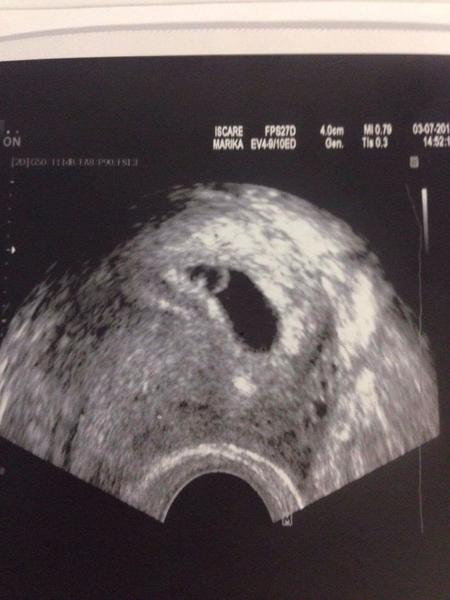

Holky, zázraky se dějí. Po 4 letech. Jsem v sedmém týdnu, srdíčko bije a vše je na dobré cestě. Počali jsme přirozeně 🙂. Jsem šťastná. Dnes mi u doktora ukápla slzička štěstí.